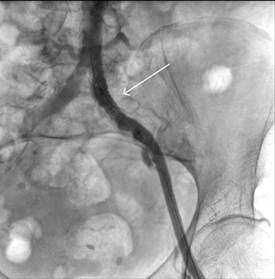

В ходе операции выполнен разрез по линии Кена в верхней трети левого бедра. Выделены ОБА, ПБА и ГАБ. В ОБА пальпировалась циркулярная атеросклеротическая бляшка. Была выполнена продольная артериотомия ОБА c переходом на устье ГАБ. Выполнена эндартерэктомия из ОБА. Решено произвести профундопластику заплатой для расширения устья ГАБ. В качестве пластического материала использован участок ствола большой подкожной вены, резецированный из этого же доступа и реверсированный. Пластика аутовенозной заплатой нитью 6/0. Пуск кровотока. В участок передней стенки ОБА выше места заплаты был установлен интродьюсер 7 фр. (рис. 2). При ангиографии визуализирована окклюзия ОПА на протяжении. После проведения мягкого гидрофильного проводника установлен баллон со стентом Balton Neptun 10 на 60 мм, выполнена ангиопластика и стентирование ОПА (рис. 3 и 4). На контрольной ангиографии восстановление просвета ОПА (рис. 5). Зафиксировано появление четкой пульсации артерий в ране. В месте доступа наложен боковой шов на ОБА. Послойные швы на рану до активного дренажа. Кровопотеря за время операции до 100 мл.

Рис. 4. Баллон сдут, стент имплантирован корректно (обозначено стрелкой)

Рис. 5. На контрольной ангиографии просвет ОПА восстановлен (обозначено стрелкой) Примечание: составлен авторами по результатам данного исследования